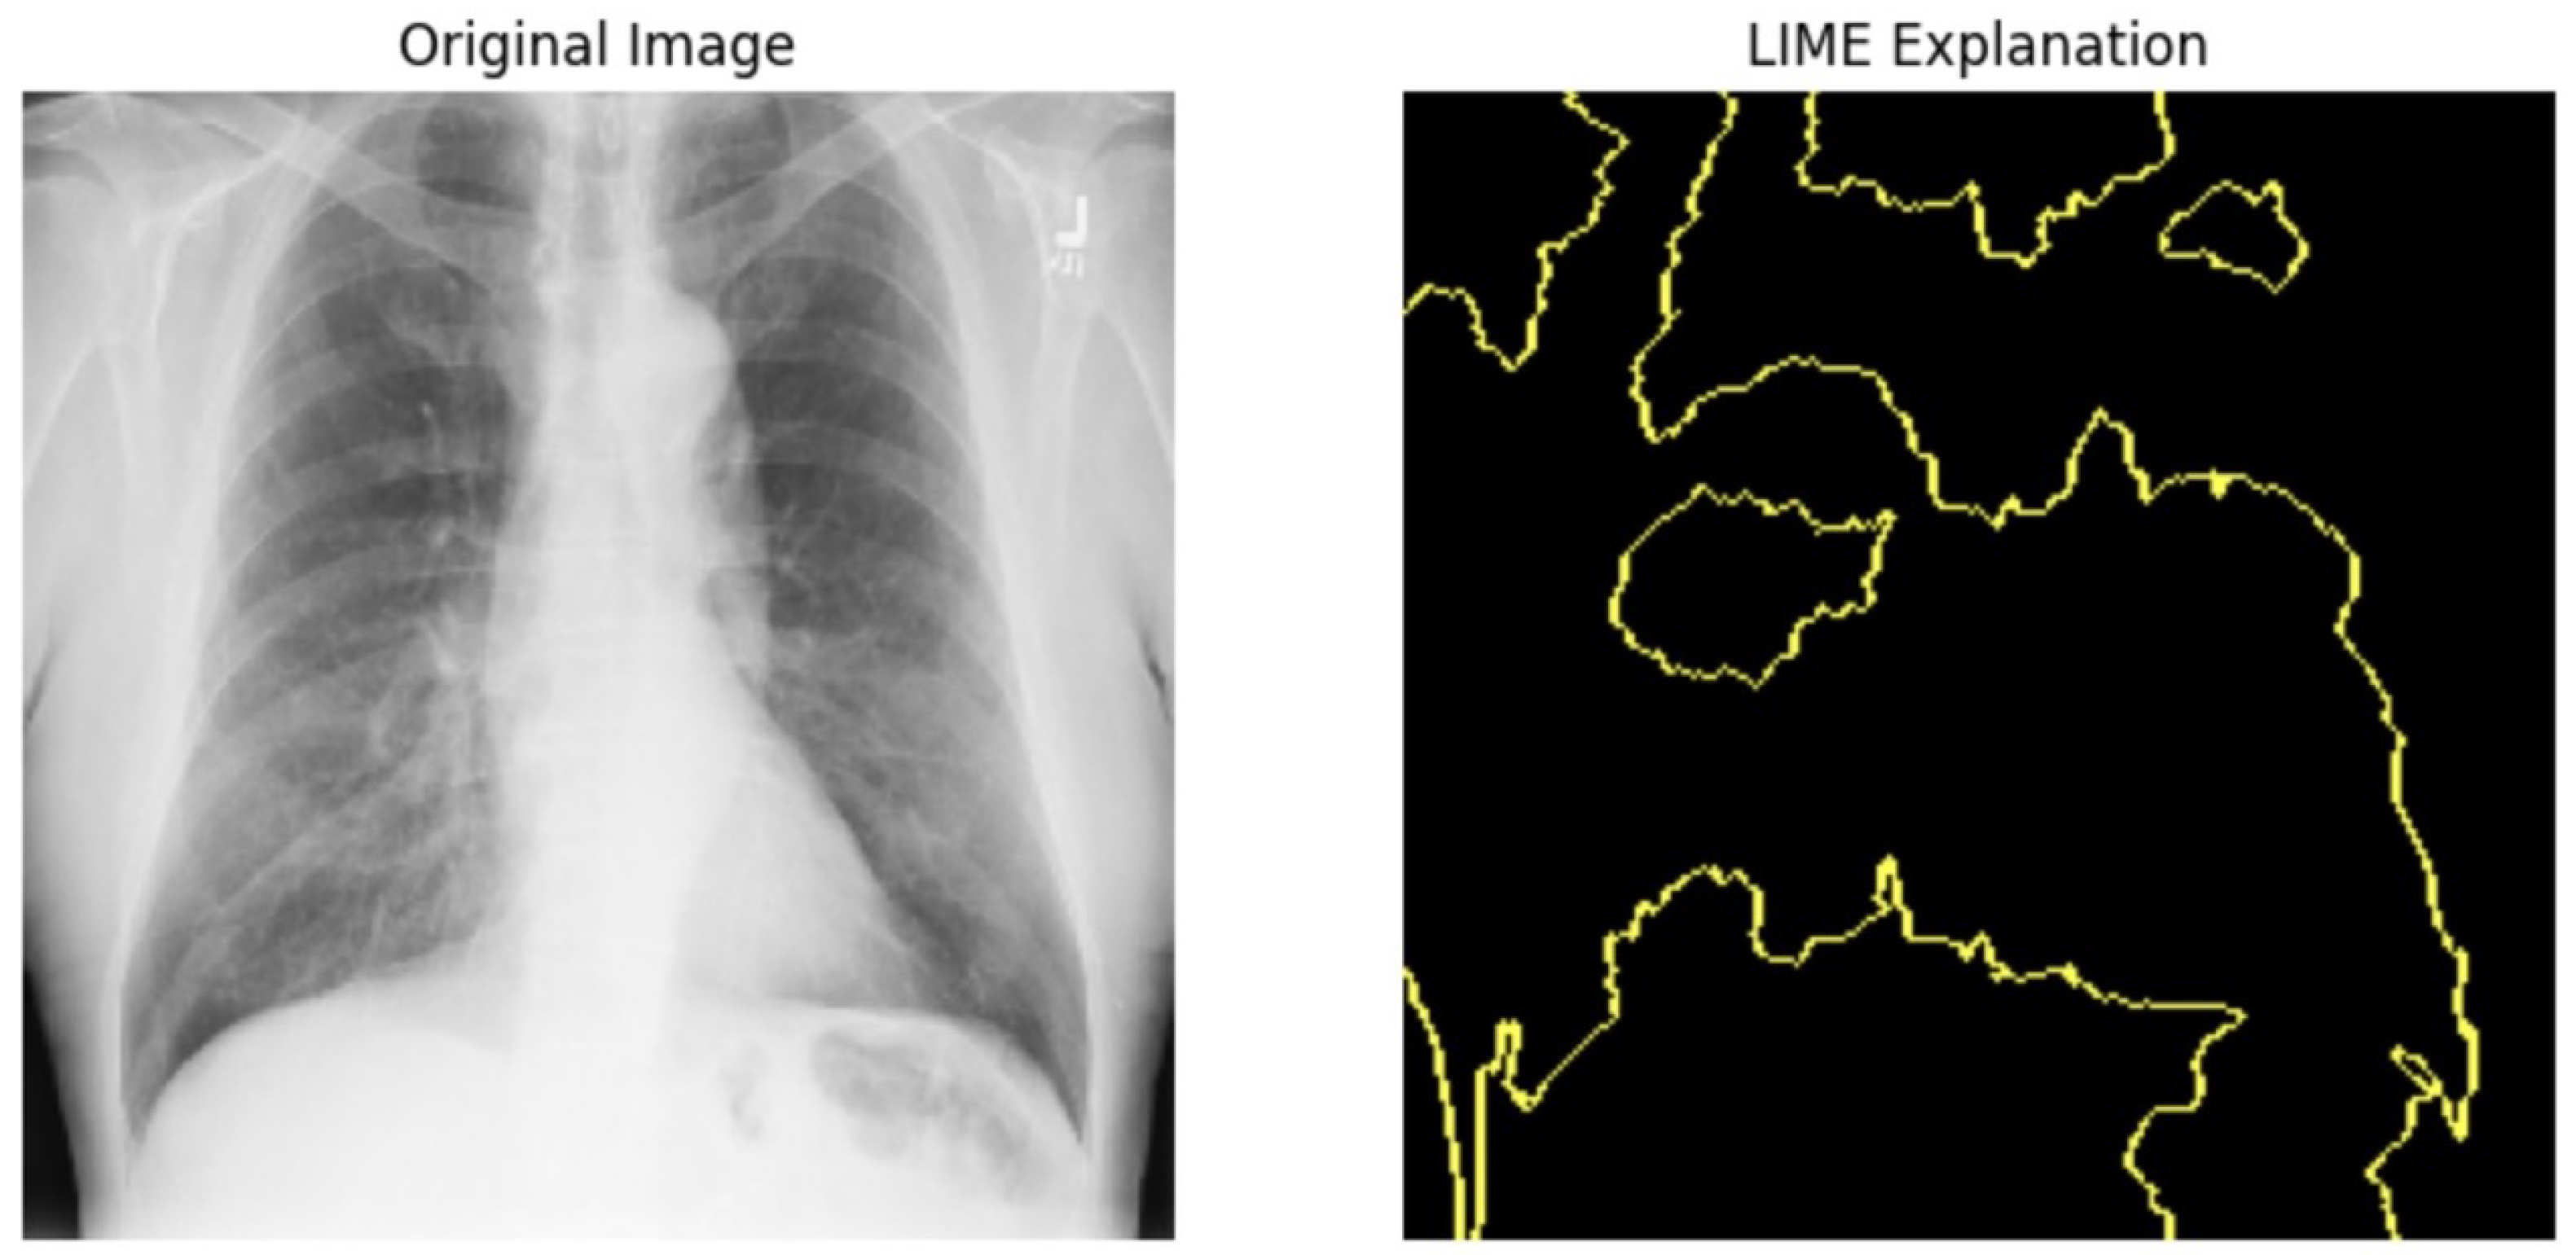

5.4.1. Local Interpretable Model-Agnostic Explanations for Clinical Validation

We applied scientific analysis on a random 7 sample, which was provided by the clinical specialist. The LIME Analysis for Image Data (a), (b), (c), (d), (e), and (f) is in Figure 22, Figure 23, Figure 24, Figure 25, Figure 26 and Figure 27. There are two parts of LIME analysis from the provided chest X-ray images to detect the disease area. Original Image and LIME explanation;

• Original Image: The patient’s thoracic cavity. It displays the typical anatomical structures of the chest, including the lungs, ribs, and heart.

• LIME Explanation: The result of applying LIME to the chest X-ray image. The yellow boundaries indicate the regions of the image that were most influential in the model’s decision-making process when determining whether the image indicated a particular condition. In this context, these regions are the parts of the X-ray that the AI model considered most important for making its diagnostic prediction.

The analysis very useful for clinicians to understand the model’s behavior and ensure that it aligns with medical expertise. The use of LIME helps in making the AI model’s interpretability decisions more transparent and interpretable. It allows medical professionals to verify whether the AI’s focus areas correspond to clinically significant regions. It also enhanced diagnostic capability of understanding which parts of the images in the AI model in refining the model further and ensures that it makes accurate and reliable predictions. This is particularly crucial in medical diagnostics where interpretability and accuracy are paramount.

Figure 22. LIME Analysis for Image Data (a) on original image to LIME explanation.